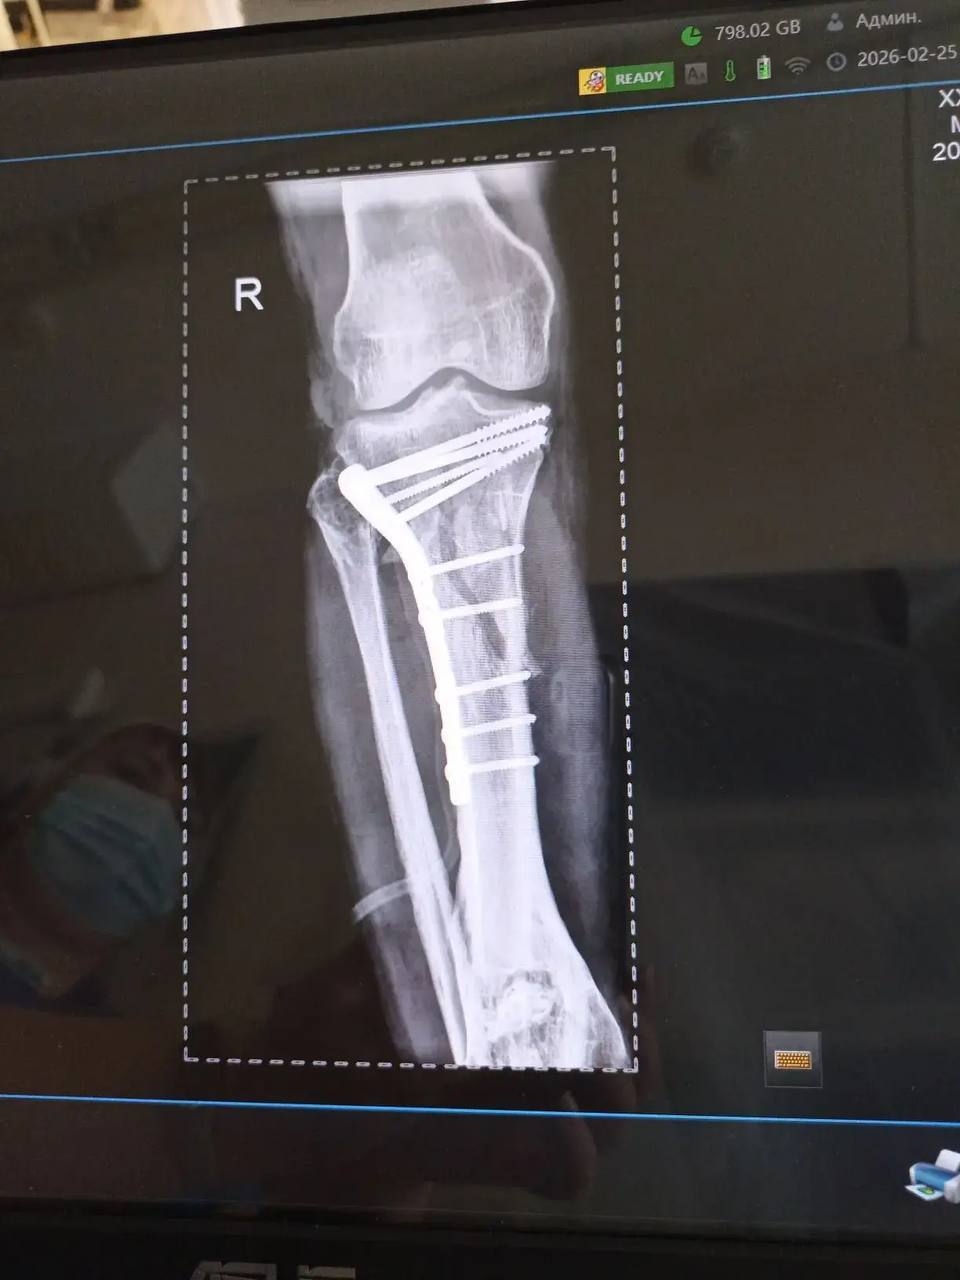

25 февраля в городскую больницу «Липецк-Мед» после тяжёлого ДТП привезли пациента с внутрисуставными переломами верхних зон обеих голеней. Ситуация осложнялась хронической анемией на фоне кровопотери, что требовало особого подхода и скорости.

Заведующий отделением травматологии Дмитрий Соколов с ассистентом врачом-травматологом Евгением Крюченковым прооперировали одновременно обе ноги с минимальной кровопотерей. Что касается переломов, то голени мужчины буквально собирали по кусочкам. Сейчас пациента уже перевели из реанимации в отделение.